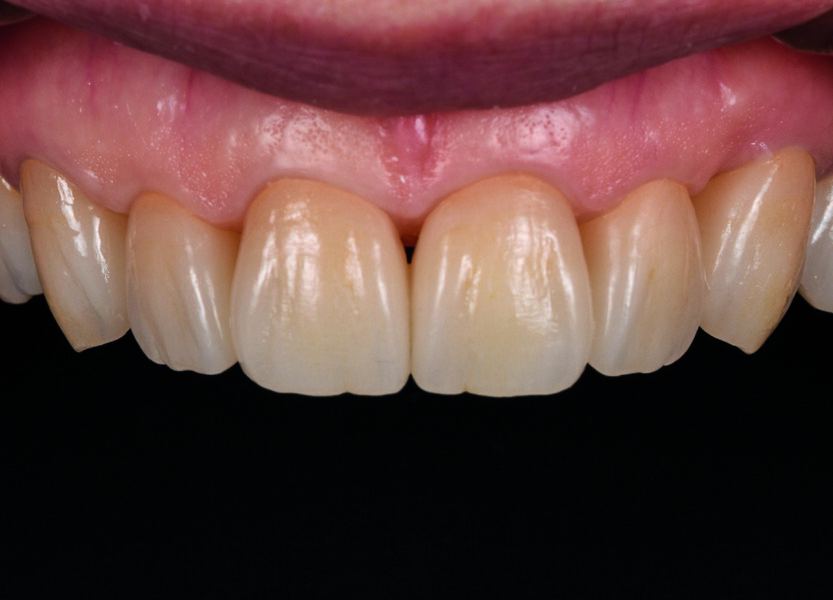

Fig. 10a : Résultat hautement esthétique et fonctionnel.

Fig. 10b : Résultat hautement esthétique et fonctionnel.

L’aspect fonctionnel est une partie importante de ma tâche journalière au laboratoire, et la combinaison du traitement virtuel de la fonction avec des matériaux efficaces, qui facilite considérablement mon travail, me donne entière satisfaction. À mon avis, la zircone, et en particulier Zolid FX Multilayer, est idéale, car elle allie esthétique et résistance (Figs. 10a et b). Toutefois, la zircone présente aussi des inconvénients ; par exemple, des contraintes inadéquates sur la couronne sont susceptibles d’entraîner une parodontite ou des problèmes condyliens, ou encore des difficultés de préparation. C’est pourquoi, dans notre travail de prothésiste dentaire, nous devons tenir compte à la fois de l’occlusion et de la fonction.

Après le frittage, je dispose ainsi de la base parfaite pour passer à la phase de finition (Figs. 7a et b). Les contacts occlusaux sont polis à la main avant le glaçage, puis j’ajoute les dernières touches de colorants et de glaçures, pour créer un brillant naturel. Selon moi, le plus grand avantage de Zolid FX Multilayer est la possibilité de reproduire précisément la forme conçue numériquement. Ce que je souhaite est en effet de réduire au maximum le besoin de retouches après le traitement, surtout dans les cas complexes (Figs. 8a et b).